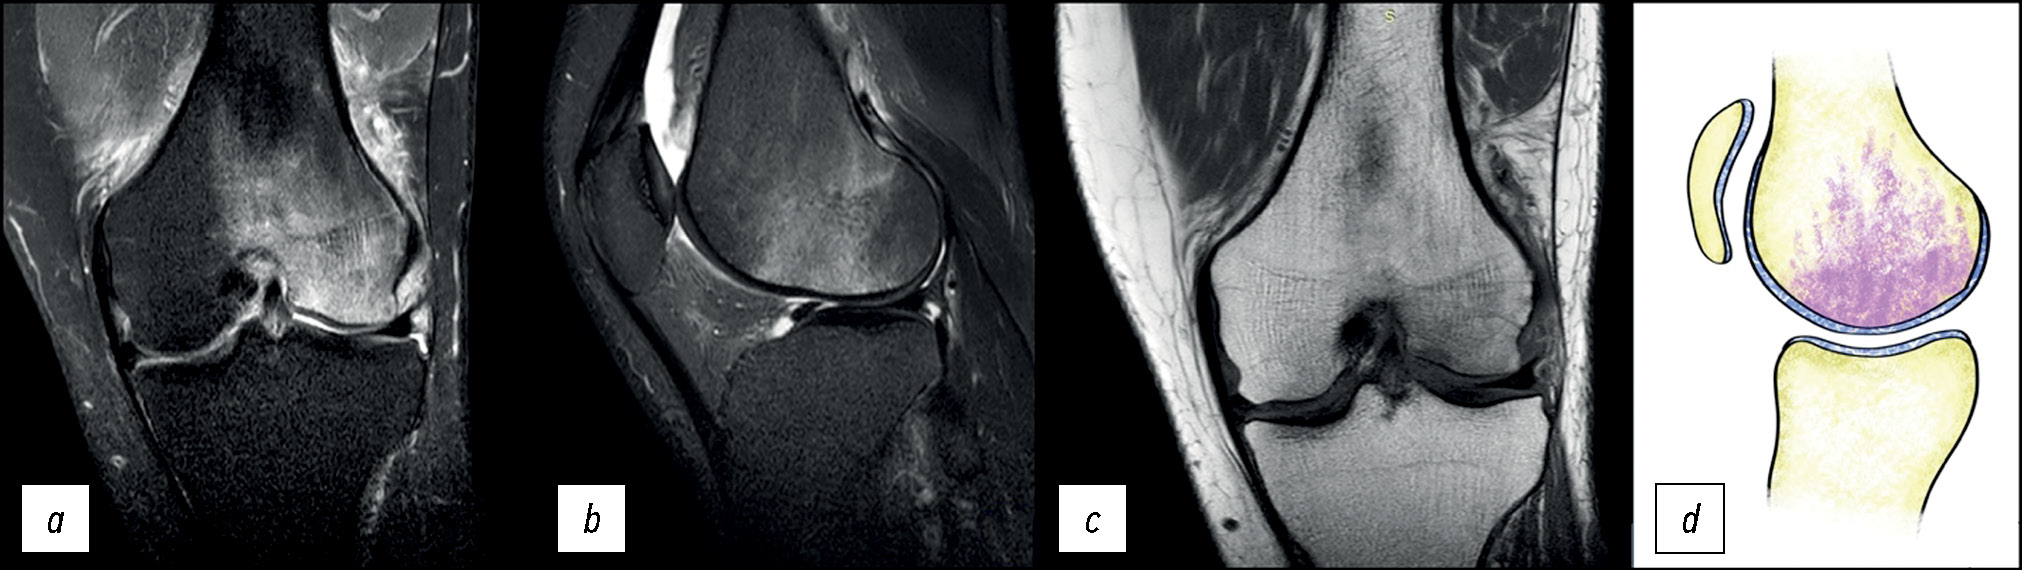

Клинический случай 7. Остеоартрит коленного сустава (Osteoarthritis knee)

Пациентка В., 60 лет, обратилась с болью в левом коленном суставе, которая беспокоит её в течение нескольких лет. На МР-томограммах (рис. 7) выявлен равномерный отёк костного мозга в области внутреннего мыщелка большеберцовой кости.

Рис. 7. МР-томограммы коленного сустава: a, b — корональная и сагиттальная проекции в режиме PD с подавлением сигнала от жировой ткани при III стадии остеоартрита, c — сагиттальная проекция в режиме Т1; d — графическое изображение. Отёкоподобное усиление сигнала костного мозга внутреннего мыщелка левой большеберцовой кости, сочетающееся с истончением или отсутствием хряща, обозначается как остеит.

Fig. 7. MRI scans of the knee: a, b — coronal and sagittal views in to suppress the signal from adipose tissue with an osteoarthritis knee, c — sagittal views in to T1. Graphic image of an osteoarthritis knee (d). Edema-like marrow signal intensity (ELMSI).

Характерными особенностями отёка кости при остеоартрите являются его равномерность, отсутствие горизонтальных линий в субхондральной области и самое важное — значительное истончение или отсутствие гиалинового хряща в области мыщелка, что отличает его от начальных стадий асептического некроза, где гиалиновый хрящ полностью сохранён.

Отёкоподобное усиление сигнала костного мозга в таких случаях обозначается термином «остеит».